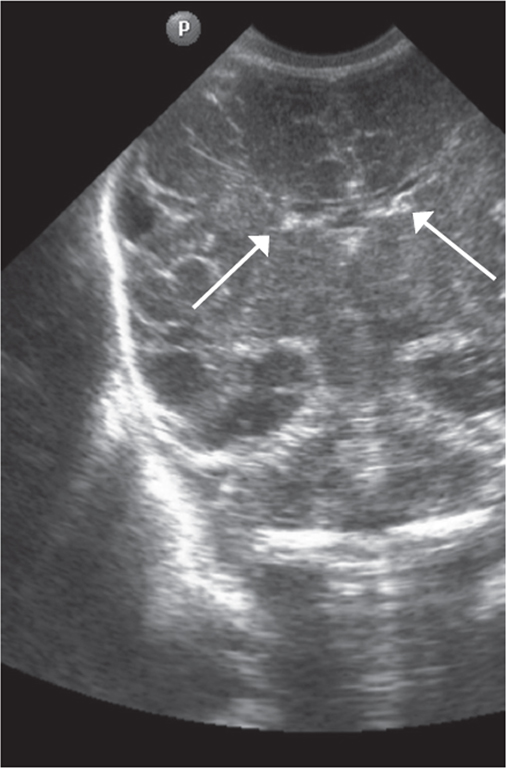

Patterns of neuroplasticity and cerebral maturation in preterm neonate can be assessed by MRI and cranial ultrasound. The score system of brain maturation includes the account of germinal matrix (GM) regression by MRI. The GM regression can be considered as pattern of neuroplasticity. There have been investigated the changes of neuroplasticity pattern or GM regression in preterm neonates with extremely low birth weight (ELBW) without intragerminal/intraventricular hemorrhages (n = 21). It is believe that the main causes of impair of GM are the intragerminal hemorrhages and hypoxia. The methods of study were cranial ultrasound (CU) and MRI. The measurement of GM was carried out by CU in anterior horn of the lateral ventricles of neonates in the study group (25-29 weeks). It was detected the GM regression in preterm neonates with increasing age, and complete GM regression to 30 week. MRI has been performed in 15 neonates from the study group on 27-38 weeks age with using the common pulse sequences – T1 WI, T2 WI and Flair. GM was detected by MRI up to 34 weeks inclusive by using the additional pulse sequence – DWI. By using common pulse sequences the GM was visualized up to 32 weeks age. Furthermore there has been pathological examination of GM in anterior horn of lateral ventricle in dead neonates from the study group (n = 3). We revealed the thickness reduction of GM in the lateral ventricles with increasing age of the dead neonates. Also we identified the delay of the GM reduction in two dead neonates 36-38 weeks age (post conceptual age) what may indicate the disorder of neuroplasticity in those preterm neonates. The performed study showed the capability of CU and MRI in examination of neuroplasticity in preterm neonates.